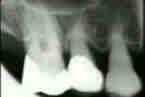

Las radiografías muestrán que

ha perdido cantidades significantes de apoyo del diente y el hueso alveolar se

redujo a más de la la mitad de las longitudes de la raíz en muchos de los dientes restantes. También puede notarse en las radiografías que la configuración del hueso alveolar es irregular con la formación de

bolsas infraóseas adyacente a los dientes. En los molares la división entre las raíces está desprovista de apoyo

de hueso. Este hecho también es obvio al examen clínico (lesión de

furcación)